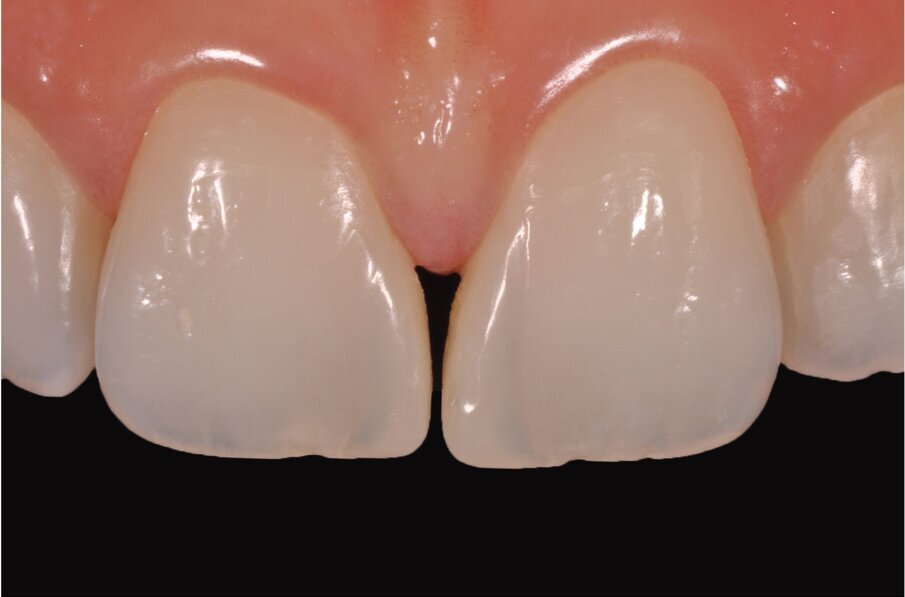

Fig. 2–4: Common troubles with a classic approach.

What were the associated problems with the older techniques including the one you used? The greatest problem for the freehand techniques, without a doubt, is the lack of cervical precision and the creation of overhangs. I have seen countless patients with bleeding gums that are not able to floss properly. Another common problem with the classical approach was the final shape. With a double emergence profile, it gave the final restoration an awkward shape (Figs. 2–4). Problems for direct diastema closure exclusively with matrices are the over contouring and the under contouring at the cervical level, discordant contact points, shifted proximal contacts, and massive excess production. To be honest, I have always been discouraged from trying that approach.